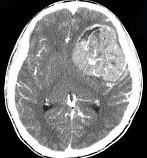

男,15岁,进行性头痛1年余,CT检查如图所示,最可能的诊断为()A.脑膜瘤B.脑血管畸形C.转移瘤D.淋巴瘤E.胶质母细胞瘤

问题 男,15岁,进行性头痛1年余,CT检查如图所示,最可能的诊断为()

选项 A.脑膜瘤 B.脑血管畸形 C.转移瘤 D.淋巴瘤 E.胶质母细胞瘤

答案 E